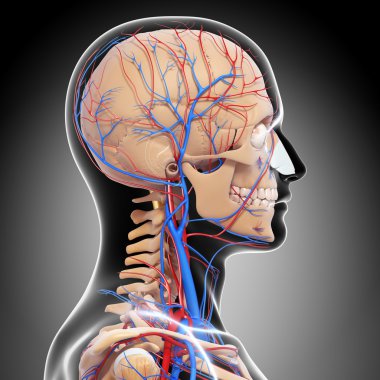

iskelet adam yan görünüm baş ve sinir sistemi

En Çok Aranan Kelimeler

resimlemeİnsanSağlıksağlıklıYaşamkanSağlık hizmetleriTıbbiboğazıçizgi filmsemboldişlerKardiyolojikalpnabızgövdeÇizimbiyolojiBilimbölümgemigerçekçiGöğüsorgBilimselanatomidiyagramPompaGergintedavülarterAtriumApexanatomikSinirlerdolaşımaortkoronerventrikülİnsan Vücududamar sistemiPulmoner fizyolojisiFiziksel bölümdolaşımı kanAnatomi gözlerBenzer İçerikler